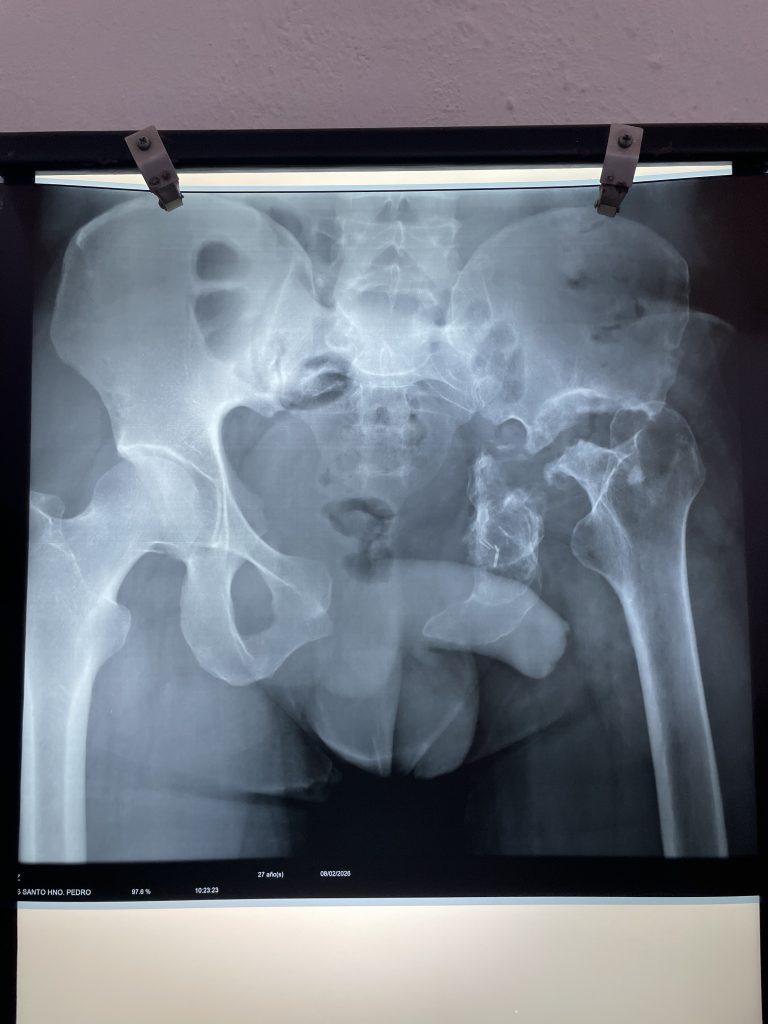

One of the most unique things about Faith in Practice is the continuity of care that we are able to provide to the patients that we treat. It’s such a comfort to the medical teams to know that the patients being operated on will have the ability to make follow-up appointments to receive the ongoing care that they need. In many cases, they can even be seen again by the same medical team that performed their surgery. Yesterday in clinic, Dr. Lorenzo Deveza saw Mario, a returning patient, who he operated on two years ago with Dr. Chappy Conrad and Priscilla Foss (anesthesia.) The case was a highly complex surgery called a hemipelvectomy, which involved removing a portion of the pelvis as well as a ewing sarcoma–a rare and aggressive cancer. To Dr. Deveza and Priscilla’s delight, Mario came for a follow-up this week and happily showed off how he could walk across the clinic floor.